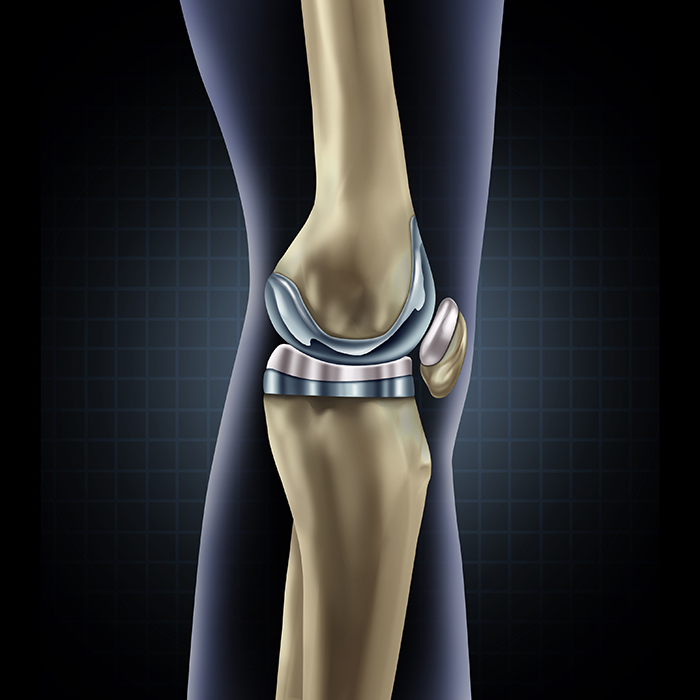

Total knee replacement (TKR), also called total knee arthroplasty, is a surgical procedure in which the worn out or damaged surfaces of the knee joint are removed and replaced with artificial parts. The knee is made up of the femur (thigh bone), the tibia (shin bone), and the patella (kneecap). The meniscus, the soft cartilage between the femur and tibia, serves as a cushion and helps absorb shock during motion. Arthritis (inflammation of the joints), injury, or other diseases of the joint can damage this protective layer of cartilage, causing extreme pain and difficulty in performing daily activities. Your doctor may recommend surgery if non-surgical treatment options have failed to relieve the symptoms.

The surgery is performed under spinal or general anesthesia. Your surgeon will make an incision in the skin over the affected knee to expose the knee joint. Then the damaged portions of the femur bone are cut at appropriate angles using specialized jigs. The femoral component is attached to the end of the femur with or without bone cement. The surgeon then cuts or shaves the damaged area of the tibia (shinbone) and the cartilage. This removes the deformed part of the bone and any bony growths, as well as creates a smooth surface on which the implants can be attached. Next, the tibial component is secured to the end of the bone with bone cement or screws. Your surgeon will place a plastic piece called an articular surface between the implants to provide a smooth gliding surface for movement. This plastic insert will support the body’s weight and allow the femur to move over the tibia, similar to the original meniscus cartilage. The femur and the tibia with the new components are then put together to form the new knee joint. To make sure the patella (knee cap) glides smoothly over the new artificial knee, its rear surface is also prepared to receive a plastic component. With all the new components in place, the knee joint is tested through its range of motion. The entire joint is then irrigated and cleaned with a sterile solution. The incision is carefully closed, drains are inserted and a sterile dressing is placed over the incision.